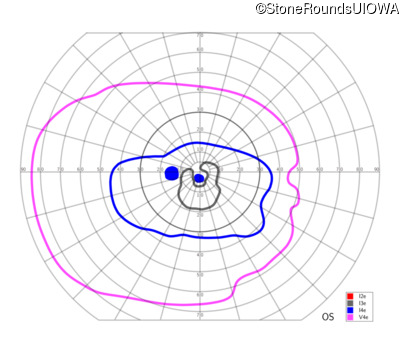

Congenital Stationary Synaptic Dysfunction (IA2g)

Congenital Stationary Synaptic Dysfunction (IA2g)

| Congenital Stationary Synaptic Dysfunction | CABP4 | Arg49Stop CGA>TGA | IVS1+1 G>T | AR |